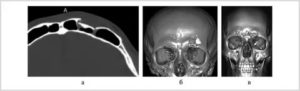

МРТ перелома передней стенки верхнечелюстной пазухи справа

Диагностика перелома стенки верхнечелюстной пазухи:

- Рентгенограмма в носоподбородочной проекции сидя – виден уровень жидкости в верхнечелюстной пазухе (почти всегда гемосинус).

- КТ

- МРТ